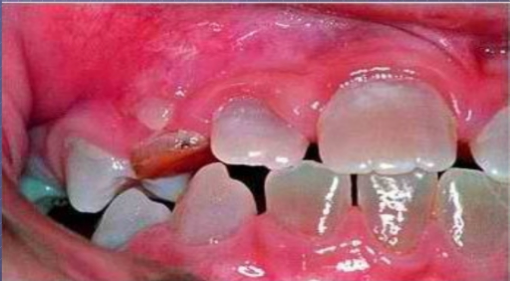

Turner’s tooth